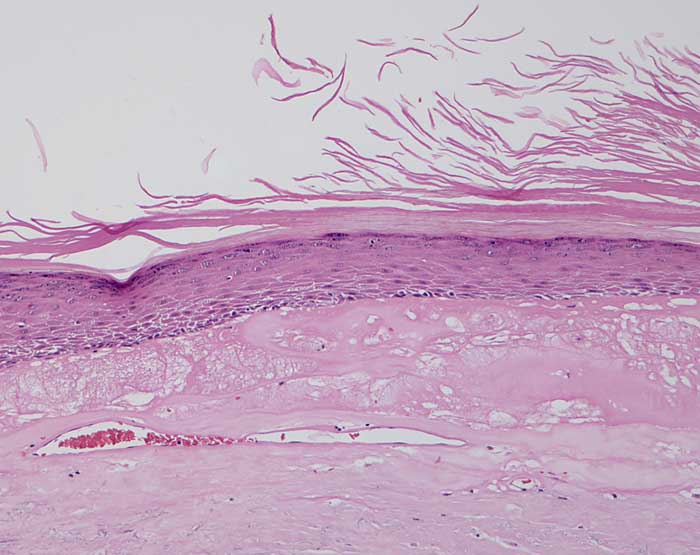

Chronische Radiodermatitis

Hyperkeratose. Zellarme hyalinisierte Dermis. Teleangiektatische Gefässe.

Fraktionierte Bestrahlung vor mehreren Jahren.